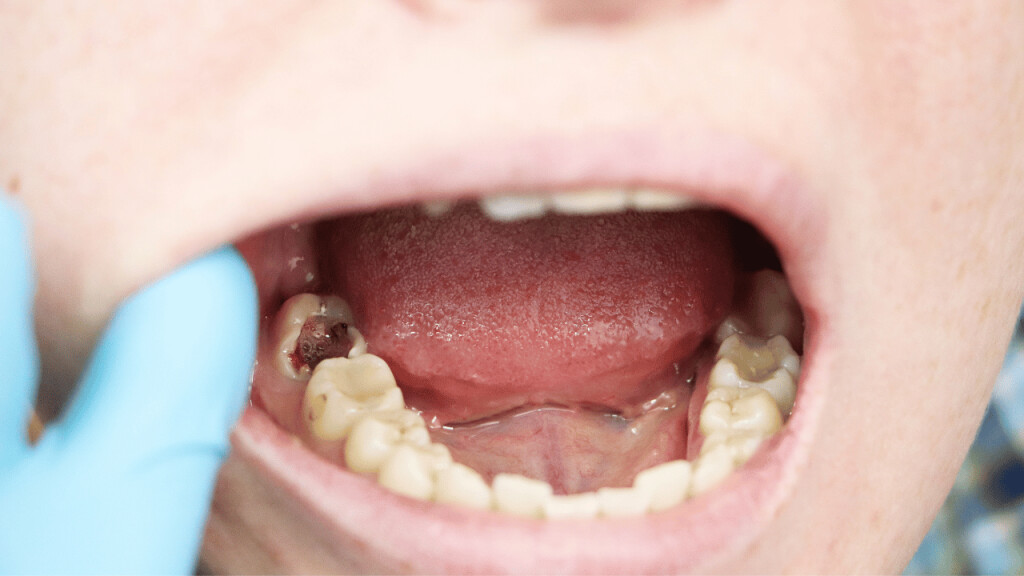

Tooth Decay

The fully impacted or the partially impacted wisdom teeth are at greater risk of tooth decay, than other teeth. This usually happens, because of the location of the wisdom tooth, especially towards the back of the mouth, which is hard to clean. Moreover, since it lies at the back of the mouth, there are chances of food getting easily trapped between the gums and the tooth, promoting the growth of bacteria.